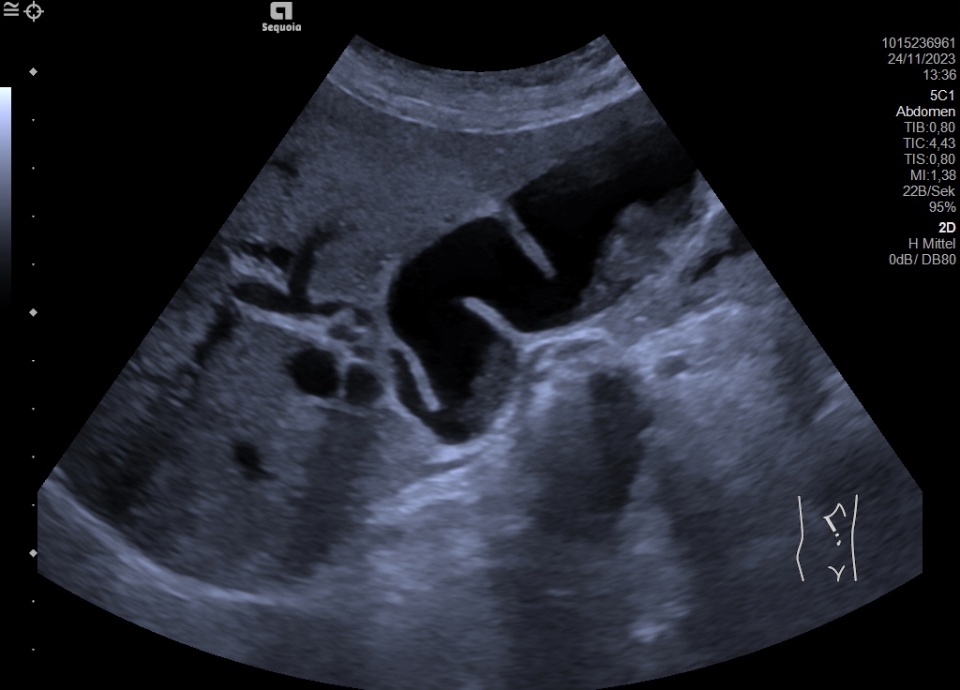

From sonographie.org

Cholestasis Atlas of Ultrasound Cholestasis Gallbladder Treatment the first step to treating cholestasis is to treat the underlying cause. Some reports indicate success in children. laboratory and often imaging tests are needed to identify the cause. we recommend etiological treatment and management of cholestasis as the treatment principle for cholestatic. (see also overview of the liver and gallbladder, gallbladder and biliary tract, and overview. Cholestasis Gallbladder Treatment.